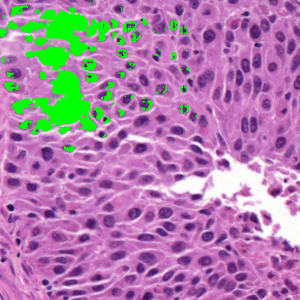

Dataset 2, released as supplementary material in [73], contains 36 digitized H&E-stained microscopy images (600 × 600 pixels) with 7931 nuclei annotated by three expert pathologists; only consensus annotations are retained. It is designed for cell nuclei detection.

Representative samples from the three datasets are shown in Fig. 1. In (a), the first frame of the synthetic video in Dataset 1 illustrates the strong illumination gradients produced by distance-dependent shading together with orientation-dependent interactions between vertex normals and the light direction. The H&E images in (b) and (c), also from Dataset 1, depict a mast cell infiltrate from a patient with non-alcoholic steatohepatitis and cirrhosis and, respectively, a sample from a patient with sclerosing polycystic adenosis of the parotid gland; the former consists primarily of purple nuclei, white cytoplasm, and pink extracellular tissue. Subfigures (d) and (e) show two examples from Dataset 2 accompanied by their ground-truth nuclei annotations, while (f) and (g) present a representative image from Dataset 3 together with its corresponding cell mask.

Figure 1: Samples from Datasets 1–3. (a) First frame of the 74-frame video in Dataset 1 (1770 × 880) with a superimposed red mesh. (b,c) H&E-stained tissue images from Dataset 1 (1000 × 750; 950 × 730). (d,e) Cell images from Dataset 2 (600 × 600) with nuclei annotations. (f,g) Image from Dataset 3 (512 × 512) with annotation.

7.2 Quantitative Results

We now assess SP using the 36 images from Dataset 2 and 50 images from Dataset 3. In our evaluation, we employ the Dice similarity coefficient (DSC) (as usual defined as the harmonic mean of precision and recall), DSC=2/(1/precision+1/recall),\mathrm{DSC}=2/(1/\mathrm{precision}+1/\mathrm{recall}), precision=tp/(tp+fp),\mathrm{precision}=\mathrm{tp}/(\mathrm{tp}+\mathrm{fp}), recall=tp/(tp+fn),\mathrm{recall}=\mathrm{tp}/(\mathrm{tp}+\mathrm{fn}), where tp\mathrm{tp} denotes the number of ground-truth points within the segmentation foreground, fp\mathrm{fp} the number of predicted regions without ground truth, and fn\mathrm{fn} the number of ground-truth points outside the segmentation foreground [73]. In Dataset 3, since pixel-level annotations were given [74], the above metrics were calculated on a per-pixel basis.

Table 1, on Dataset 2, shows that SP obtained the highest DSC (88.78), which is higher by 5.90, 7.09, 8.31, and 22.46 compared to SAM, ZZ, SMST, and AR, respectively. The segmentation time of SP was 14.55s, approximately twice that of SAM (the second fastest method without considering pre-processing times), and more than one order of magnitude lower than the level-set methods AR and ZZ. While AR and ZZ need user-specific markers as input (the pre-processing time indicated as \infty), SAM needs to load the pre-trained model (6.09s) while SP and SMST need to generate the superpixels in the pre-processing step (0.08s). Figure 11 shows the resulting segmentations for two example images from Figs. LABEL:fig_sub:he3_image and LABEL:fig_sub:he4_image from Dataset 2. The segmentations reflect the trends observed in Table 1, with SP achieving the highest DSC and segmentation times exhibiting a similar relative order.